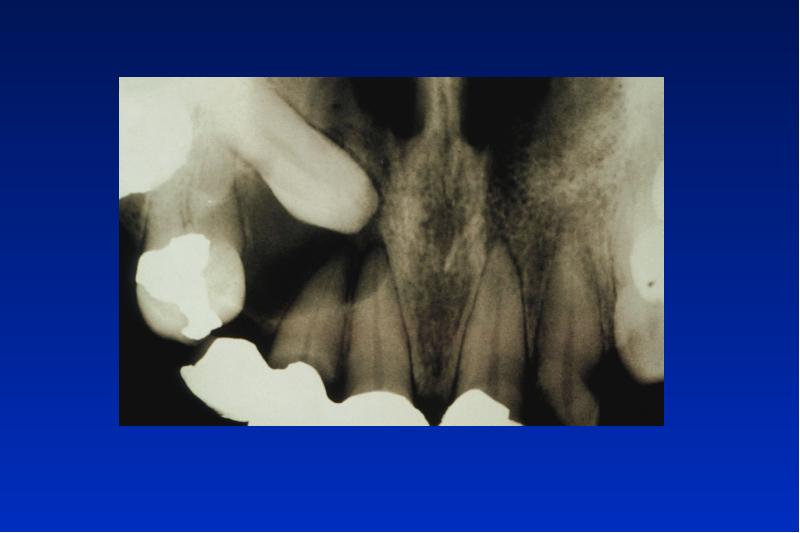

- 21. Odontogene Keratozyste Lok: UK Alter: 20 - 30, 50 - 60